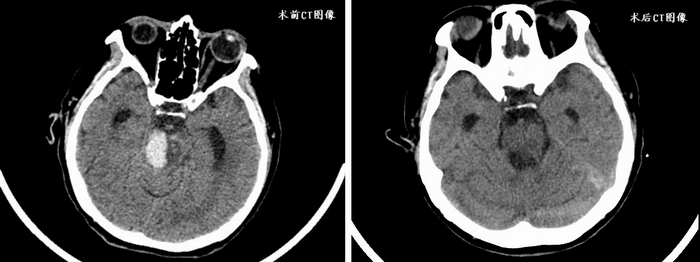

患者刘女士因突发意识障碍于我院神经外科急诊就诊,进行了头颅CT检查提示脑干出血,出血量约为15ml。

脑干是神经反射与传导的重要枢纽,也与人的意识、呼吸、心跳密切相关,所以该区域以往被认为是手术禁区。然而随着显微外科技术的进步,禁区逐渐被突破,已有一些脑干病变患者可以接受手术治疗,并且在术后获得良好的生活质量。但是脑干区域的手术难度和风险仍然极大,尤其脑干出血是神经系统危急重症,出血量越大死亡率越高,因此如何快速为患者制定恰当救治方案是治疗的关键。神经外科团队针对此患者病情展开讨论,讨论后认为应对患者的脑干血肿进行穿刺引流。为了精准穿刺血肿,达到最佳的引流效果,神外团队在机器人辅助下制定穿刺靶点、合理规划手术路径,同时在医学影像科、麻醉科和手术室的协作下顺利完成了血肿穿刺。术后刘女士复查头部CT提示脑干内血肿引流效果满意,意识状态明显好转,并可以完成指令性动作,现在她正在接受康复治疗。